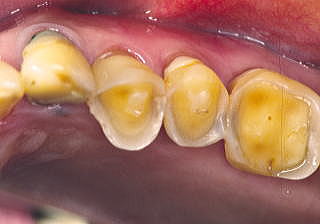

■症例3:酸食症 Acid Erosion

患者:75歳、女性。

ドレッシング、オレンジ、“酢の物”さらに黒酢が好物で、毎日常用。数十年の結果、大切なEnamel質は消失し、咬合高径まで低くなってしまった